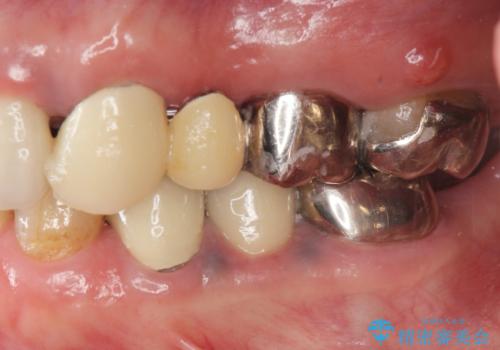

- 長年使用し、見た目の気になってきた金属製のブリッジのやりかえを希望され来院されました。

老朽化した金属製のブリッジを丁寧に除去したのち、金属を用いない審美性の高いセラミック製のブリッジでのやりかえを計画します。